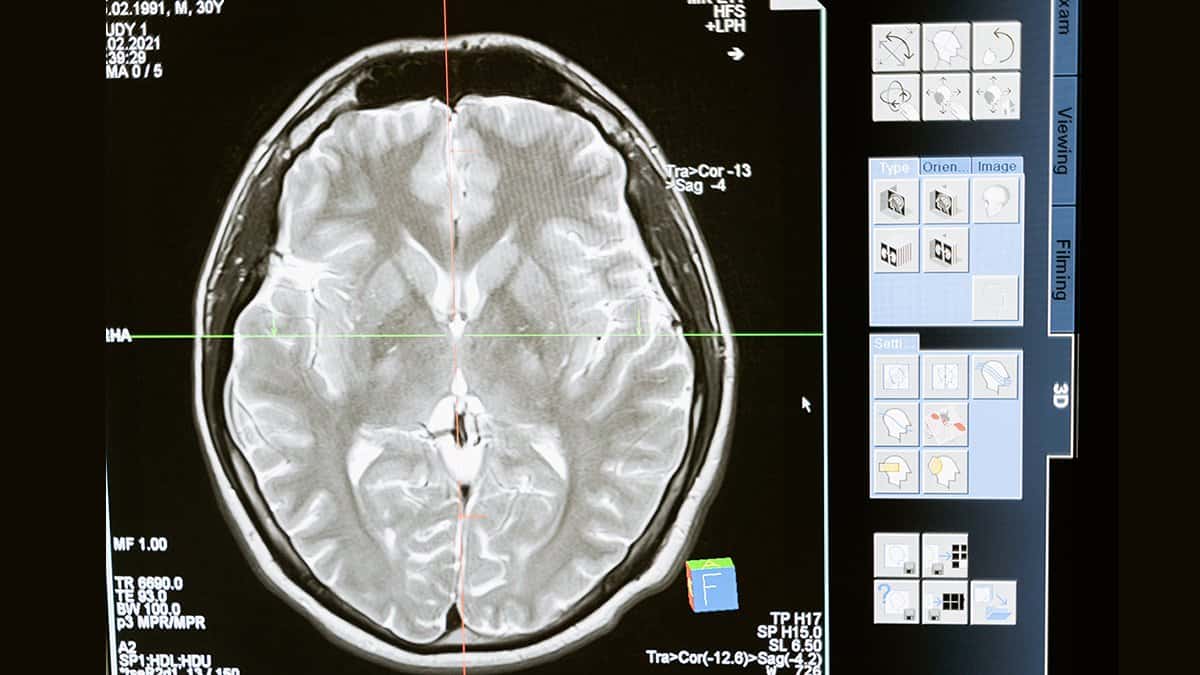

Je kunt heel eenvoudig preventief medisch onderzoek laten verrichten. Je hebt hiervoor geen doktersverwijzing nodig. Maar welke onderzoeken kun je dan laten uitvoeren? Middels welke medische onderzoeken kun je inzicht krijgen in jouw gezondheid? Je kunt jezelf misschien beter afvragen welke onderzoeken je niet preventief kunt laten uitvoeren. Er zijn namelijk tal van verschillende soorten medische onderzoeken beschikbaar. Ben je benieuwd hoe het met jouw hersengezondheid gesteld is? Dan kun je hiervoor een MRI hersenen laten uitvoeren.

Wil je weten of jouw hart gezond is? Dan behoort een uitgebreid cardiologisch onderzoek tot de mogelijkheden. En wil je graag een algemeen beeld van jouw algehele gezondheid krijgen? Dan biedt een laboratoriumonderzoek en/of een bodyscan uitkomst. Er zijn diverse onderzoeksmethoden voor handen waarmee inzicht in jouw gezondheid kan worden verkregen.